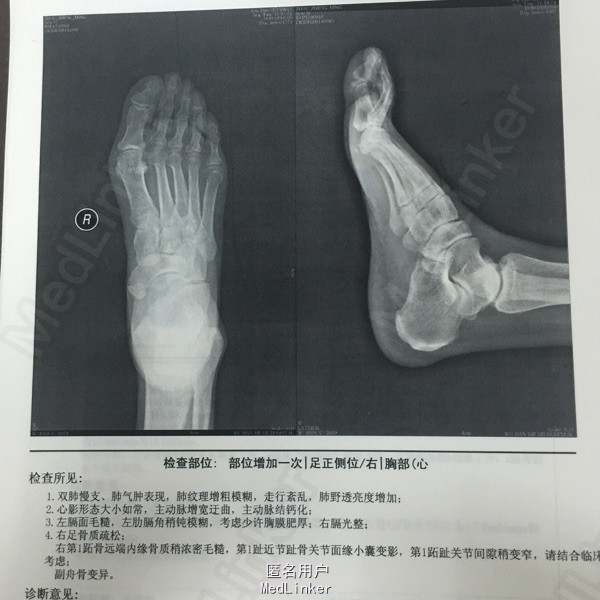

查体:右膝关节水肿,皮温稍高,压痛(+),活动无明显受限,右踝关节水肿,右足第一跖趾关节红肿,皮温稍高,压痛(+)。。辅助检查:血钾 2.52mmol/L,尿素氮8.96mmol/L,肌酐149.4,尿酸506.2;肾脏ECT提示:双肾位置、大小正常,双肾血流灌注稍降低,肾小球滤过功能减低,左、右肾GFR分别为17.9mi/min和17.1mi/min,双肾肾盂肾盏排泄滞留。右足平片:右足骨质疏松;右第1跖骨远端内缘骨质稍浓密毛糙,第1趾近节趾骨关节面缘小囊变影,第1跖趾关节间隙稍变窄。

诊断:1、痛风 痛风性关节炎急性期 2、高血压病3级 很高危 3、慢性肾功能不全 4、发热原因待查:肺部感染 治疗:低嘌呤饮食,碱化尿液、抗感染、补钾、降压,考虑口服别嘌醇引起血小板减少,改用非布司他片口服,同时口服安康信、药用碳,外用扶他林软膏。